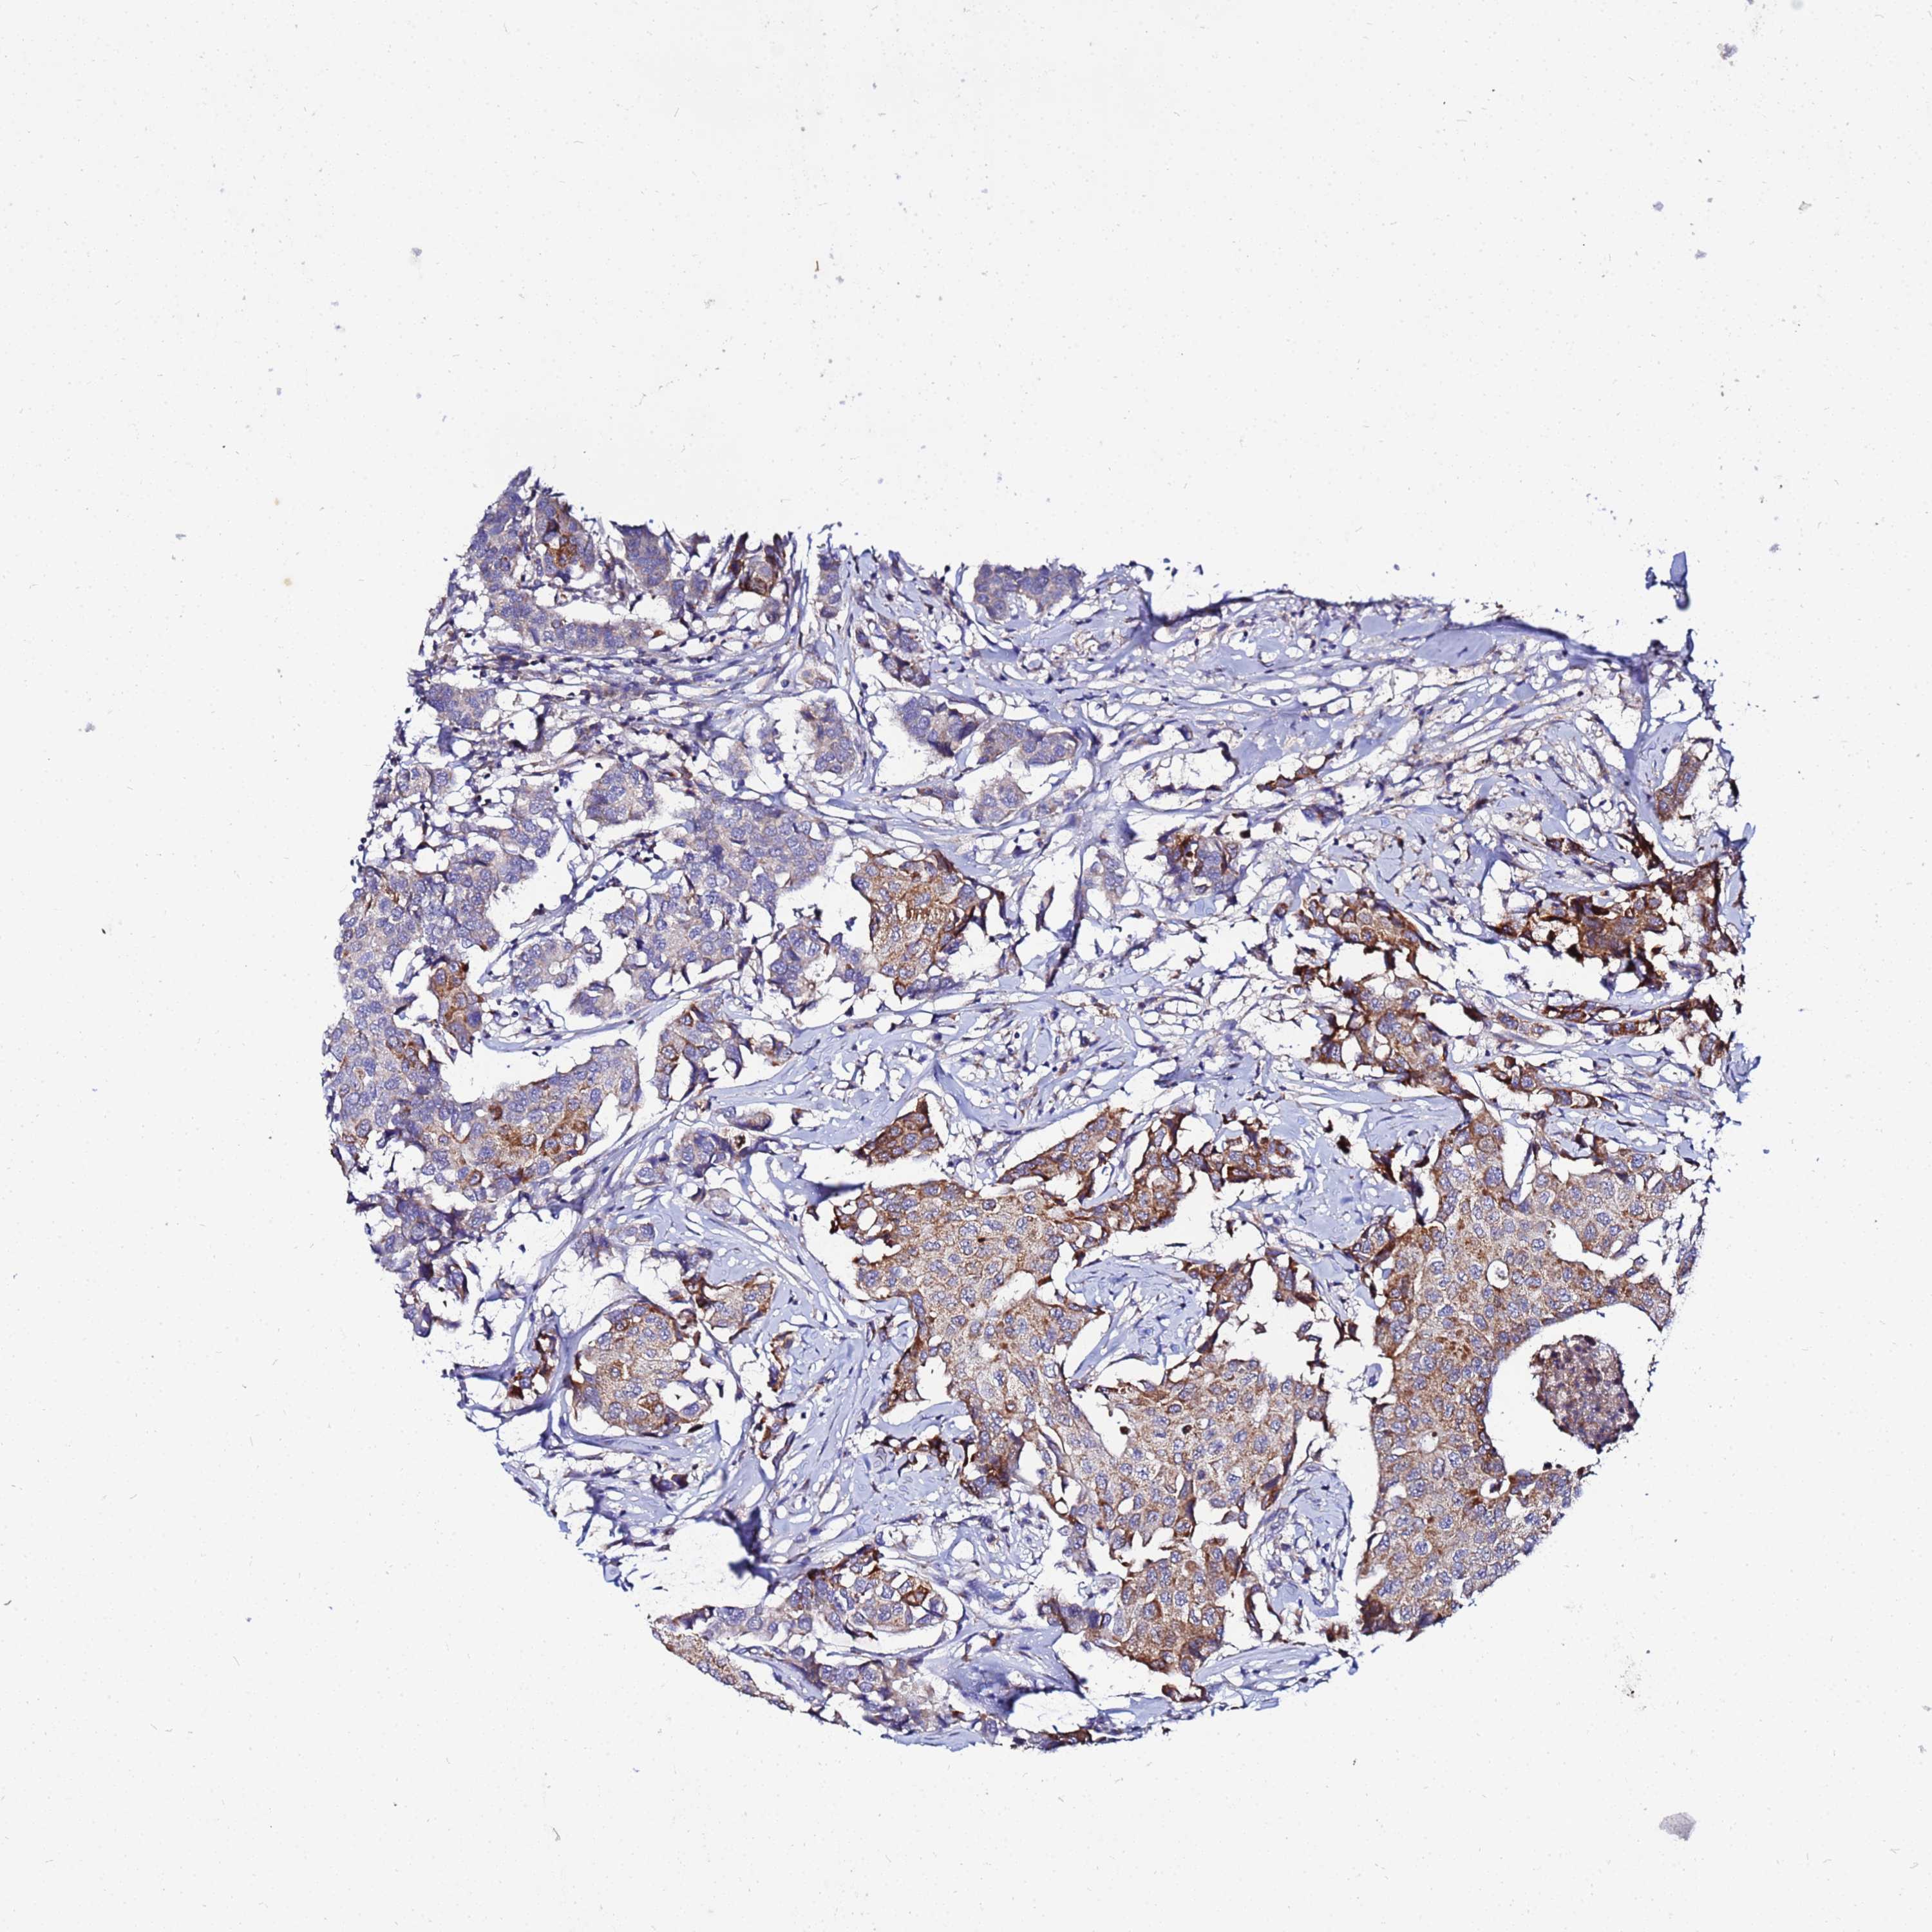

CANCER BREAST CANCER Show tissue menu

BRCA TCGA BRCA VALIDATION PROTEIN EXPRESSION